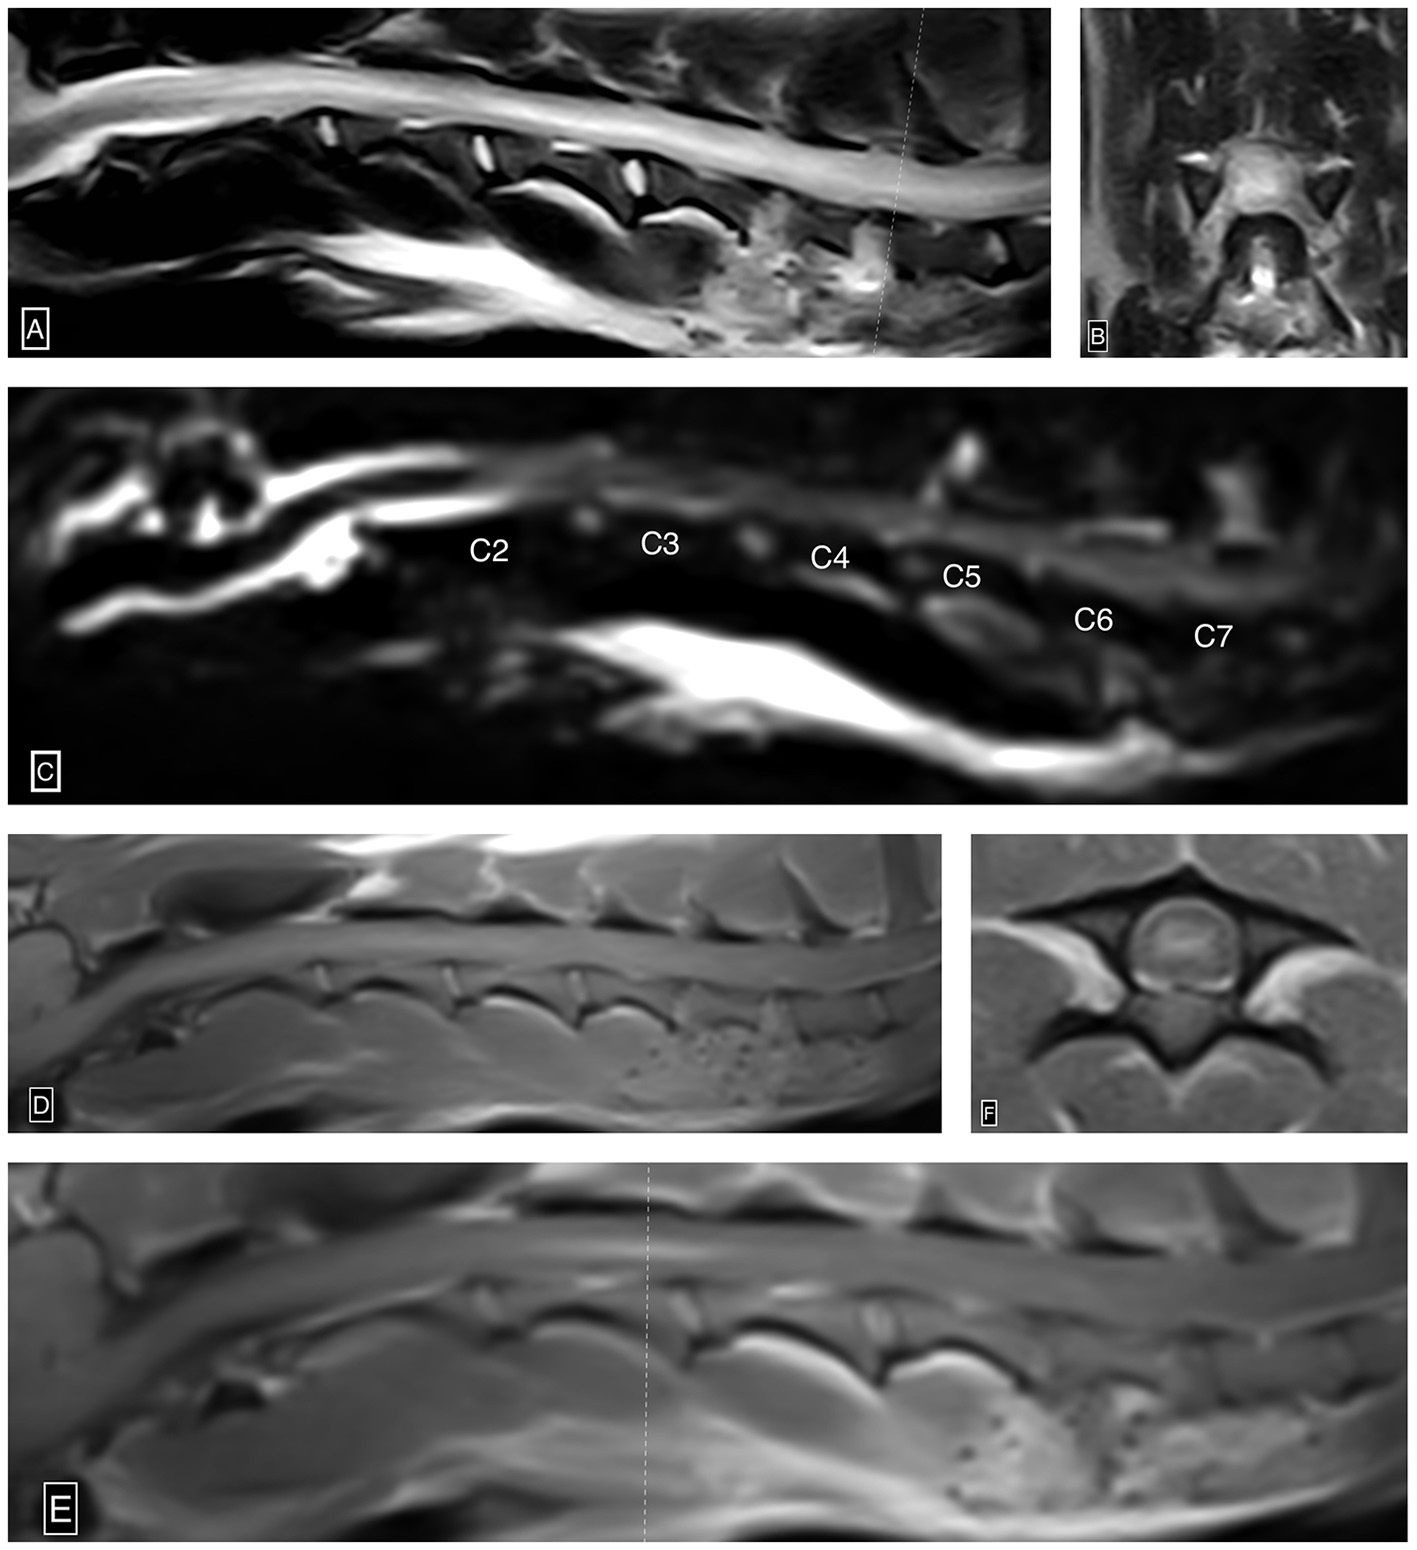

Figure 2

Ascending/descending cervical myelomalacia. Sagittal (A) and transverse (B) T2W images show severe diffusely and heterogeneously increased intramedullary T2W signal intensity within the cervical spinal cord centered over the gray matter. Notably, the recent C5-6 and C6-7 hemilaminectomy sites characterized by ostectomy and local soft tissue thickening and increased signal intensity (A, B). Sagittal HASTE image (C) shows complete and circumferential attenuation of the cervical subarachnoid space from the level of mid-C2 beyond the caudal limit of the study (level of T2), suggestive of extensive spinal cord swelling. Pre-contrast sagittal T1W (D), post-contrast sagittal T1W (E), and post-contrast transverse T1W (F) images demonstrate ill-defined and heterogeneous intraparenchymal contrast enhancement centered over the gray matter from the level of C2-3 through mid C4. The dotted line (E) denotes the axis by which the post-contrast T1W image is acquired.

The patient subsequently underwent an MRI (Esaote MR Vet Grande 0.25 tesla; Geneva; Italy) of the neck. Transverse and sagittal MRI images of the neck were acquired in T2-weighted (T2W), T1-weighted (T1W), T2W*, and fluid-attenuated inversion recovery (FLAIR) sequences pre- and post-gadolinium administration. This study demonstrated severe diffusely and heterogeneously increased intramedullary T2W signal intensity within the spinal cord parenchyma centered over the gray matter extending from the level of C1-2 caudally beyond the caudal limit of the cervical spine study at the level of T2 (approximately over 18 cm, nine times the C2 vertebral length). This abnormal cervical intramedullary hyperintensity caused near complete obliteration of the gray matter to white matter distinction and central canal conspicuity. Within the spinal cord, gray matter extending from the level of C2-3 through C4, there was moderate ill-defined and heterogeneous intraparenchymal contrast enhancement. There was complete and circumferential attenuation of the subarachnoid space extending from the level of mid-C2 caudally beyond the caudal limit of the cervical spine study (level of T2), consistent with severe spinal cord swelling. There was no evidence of a T2W*susceptibility artifact identified in the study. These MRI findings were consistent with imaging findings associated with progressive myelomalacia in the thoracolumbar spine, as well as ischemic necrosis (Figure 2). At this point, given the primary suspicion of progressive myelomalacia along with the grave prognosis, the owners opted for euthanasia. A measure of 11 ml of IV pentobarbital was administered, and cardiac arrest was confirmed with auscultation. The brain and cervical spinal cord to the level of T1 were submitted for histopathology interpretation.